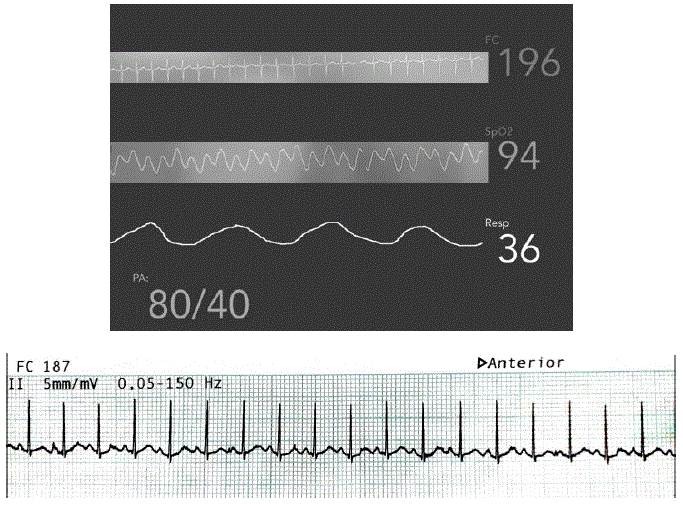

Menina, 7 anos de idade, previamente hígida, apresenta quadro de febre há 1 dia de até 39,5°C, mal-estar e hipoatividade. Foi admitida no Pronto-Socorro letárgica, sendo levada à sala de emergência. Na avaliação primaria, estava febril, sonolenta, porém responsiva ao chamado, hidratada. Apresentava extremidades frias, pulsos finos e tempo de enchimento capilar de 6 segundos. Ausculta pulmonar e cardíaca sem alterações, abdome indolor, sem visceromegalias. Abaixo os dados de monitorização do paciente.

Qual é a conduta imediata?